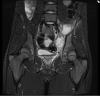

Figure 1

T2-weighted MRI of the pelvis in coronal view indicating effusion of the left sacroiliac joint associated with surrounding oedema suggestive of left sacroiliitis.